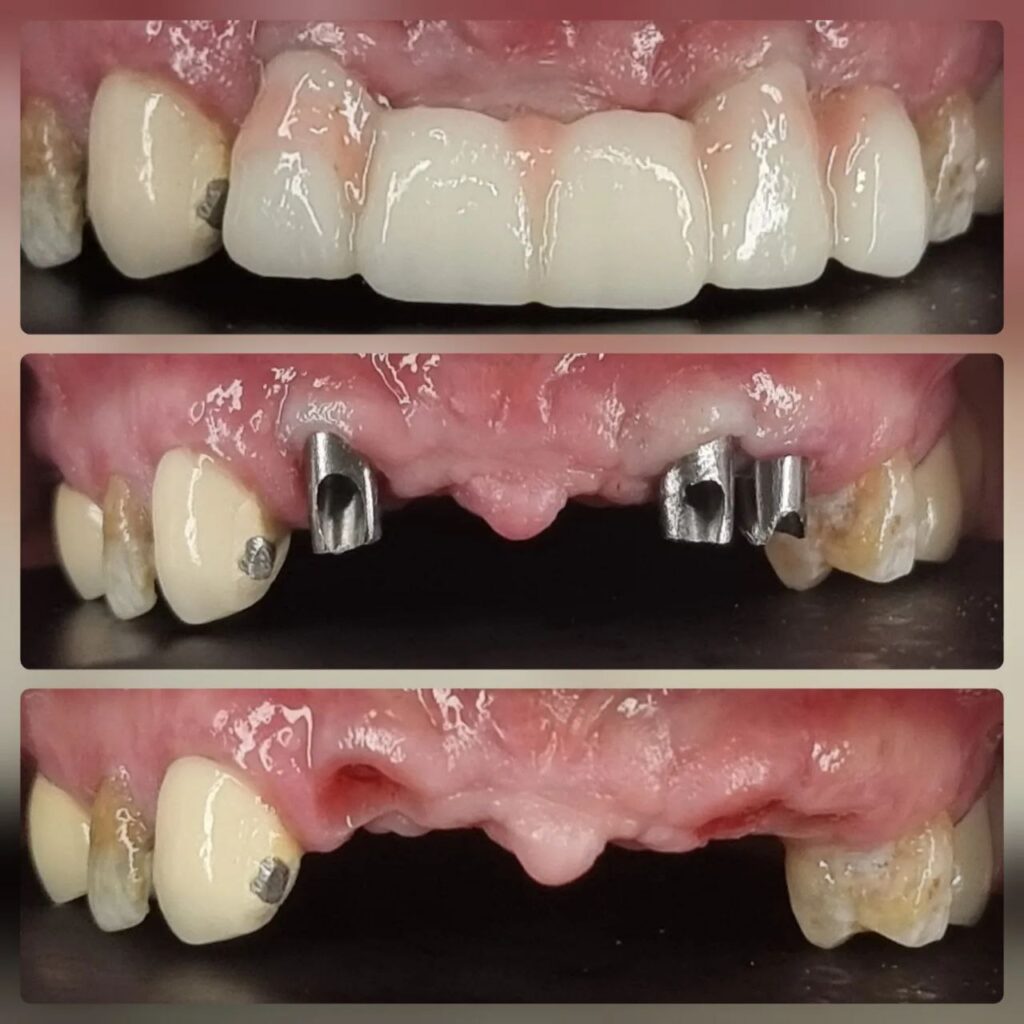

کاشت ایمپلنت دندان

اطمینان حاصل کردن از اینکه دندانهایتان به نحوی زیبا و طبیعی جایگزین شدهاند، از اهمیت بسیاری برخوردار است. ایمپلنت دندان به عنوان یک روش درمانی دائمی در دندانپزشکی شناخته میشود که حاصل آن، یک دندان زیبا و طبیعی در دهان شما خواهد بود.

هرچند که این روش درمانی هزینهی بیشتری نسبت به روشهای دیگر دارد، اما ارزش زیبایی که ایجاد میکند، قابل انکار نیست. ایمپلنتها به قدری شبیه به دندانهای طبیعی هستند که به سختی میتوان آنها را از دیگر دندانها تشخیص داد.